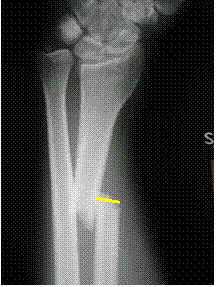

One shaft width

ulnar displacement

of distal radius

relative to proximal

shaft